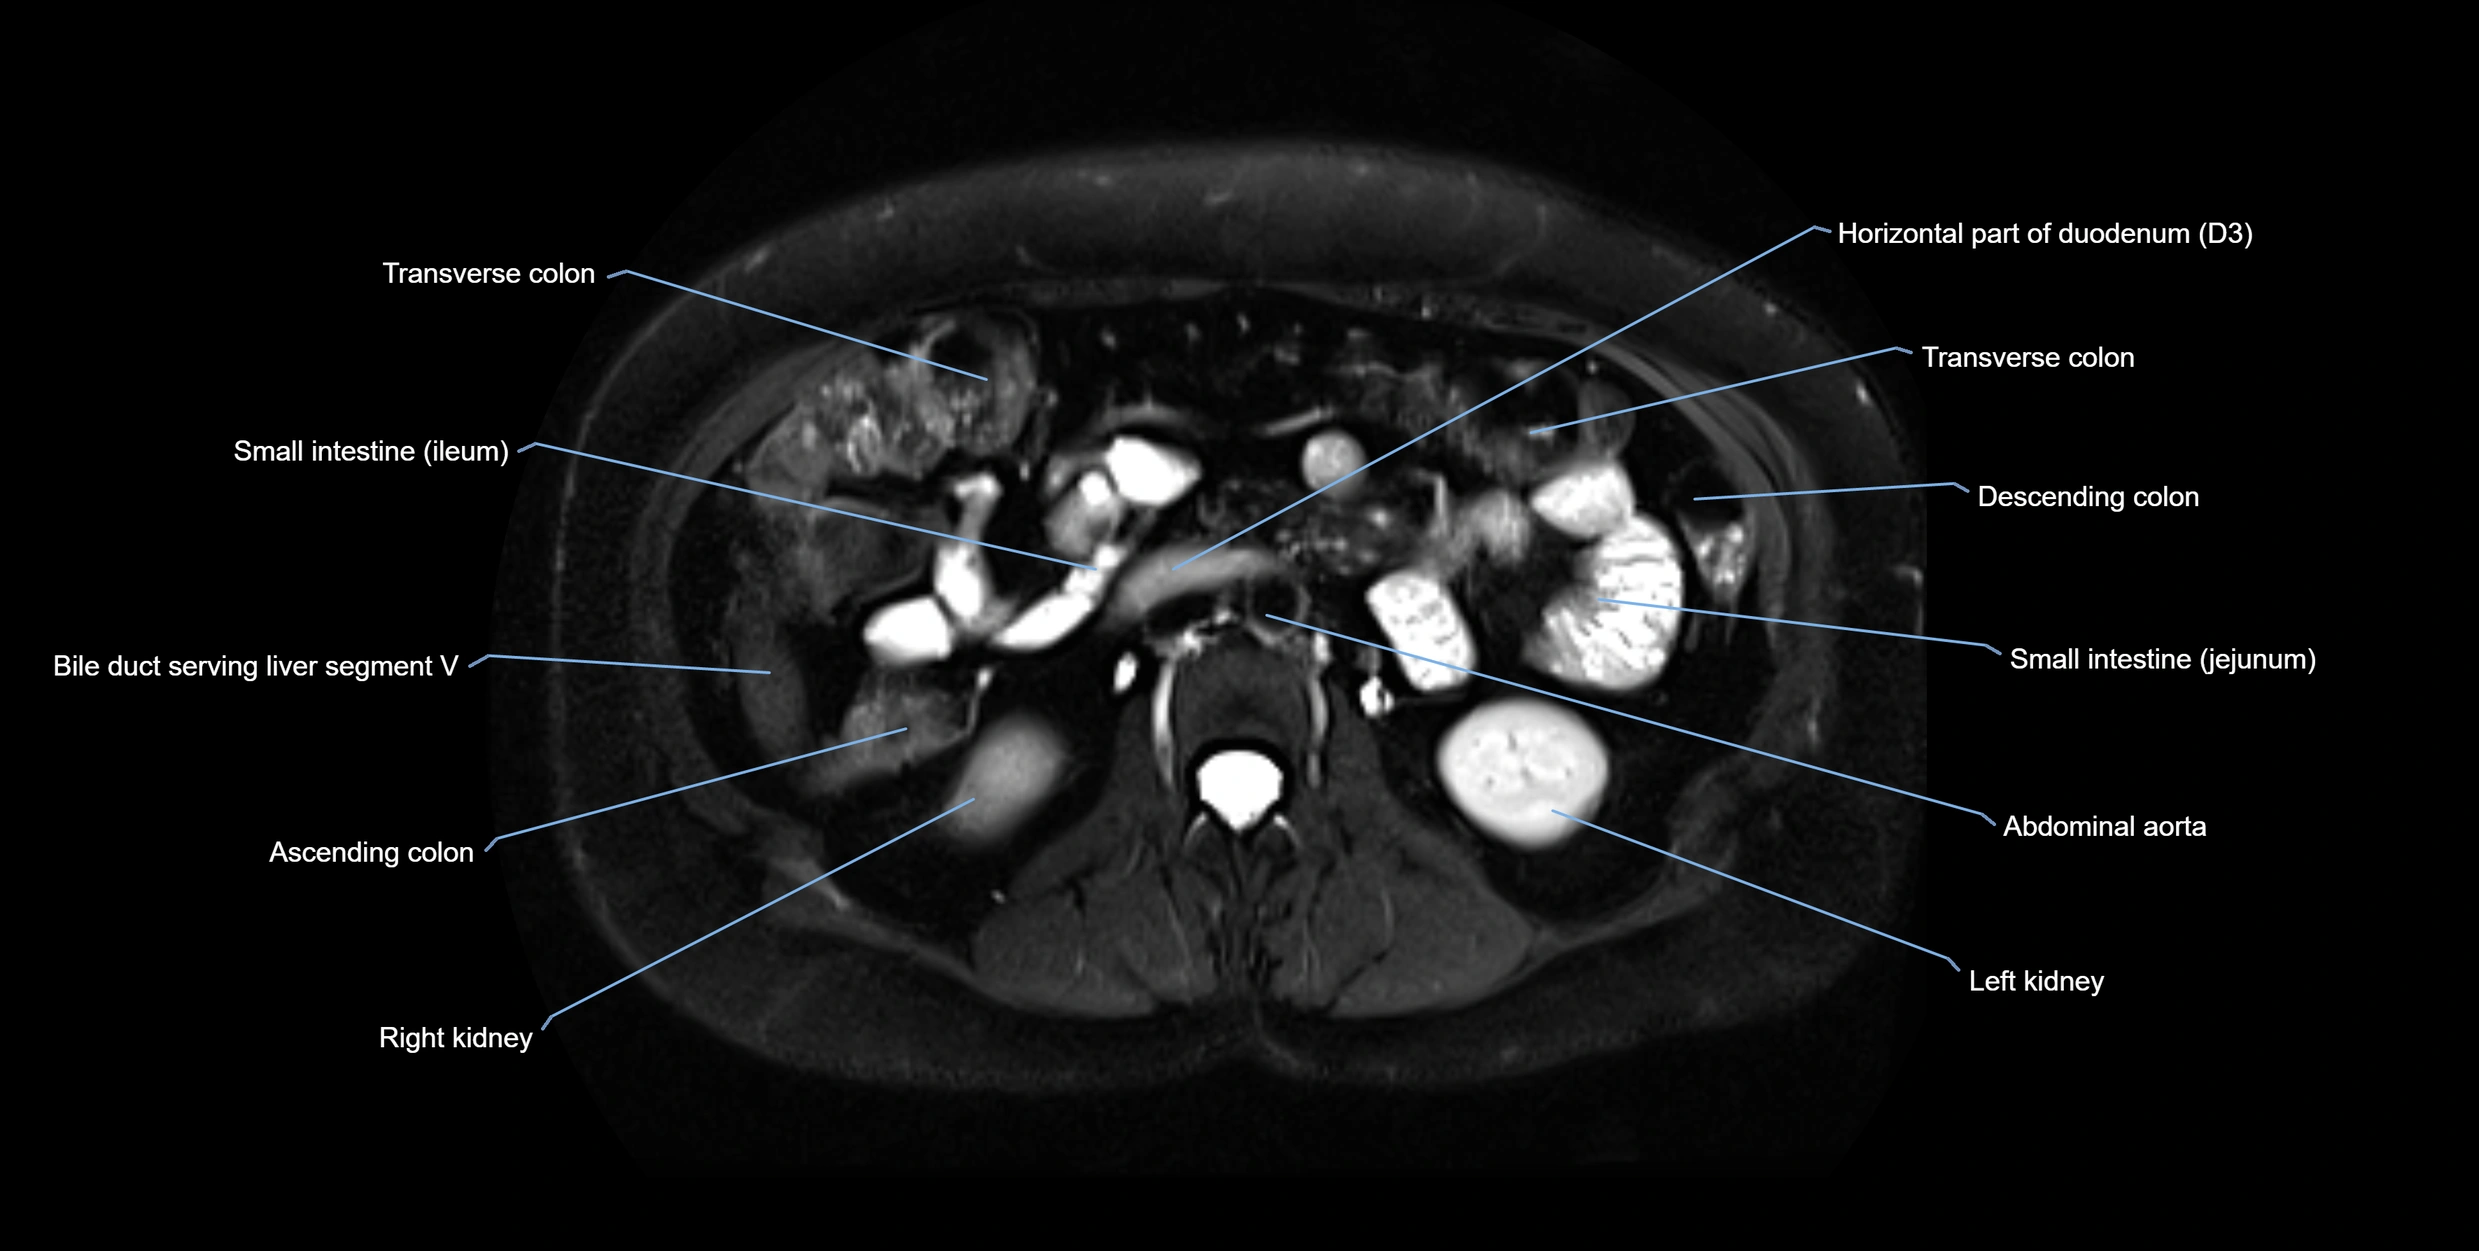

MRI image

image